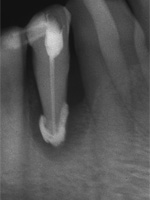

Patientin(60):

Dieser rechte Eckzahn meldete sich aber erst 3 Jahre später, weshalb er anfangs auch nicht sonderlich ernst genommen wurde.

Erst wiederholtes Lamentieren machte klar, es müssen schon Massnahmen sein, Vertrösten reicht nicht mehr allein.

Wurzelkanalbehandlung und Resektion wurden innerhalb eines Monats abgearbeitet und sind hier erwähnenswert auch nur vielleicht, weil von Natur aus lange Eckzahnwurzeln intra operationem subjektiv endlos lang werden können und weil hier

der Behandlungserfolg 10 Jahre nach dem Eingriff durch eine neue Aufnahme belegt werden kann. Wie alle anderen Aufnahmen auch,

1 und 2 sind von 2000, die 3. ist vom 10.06.2010